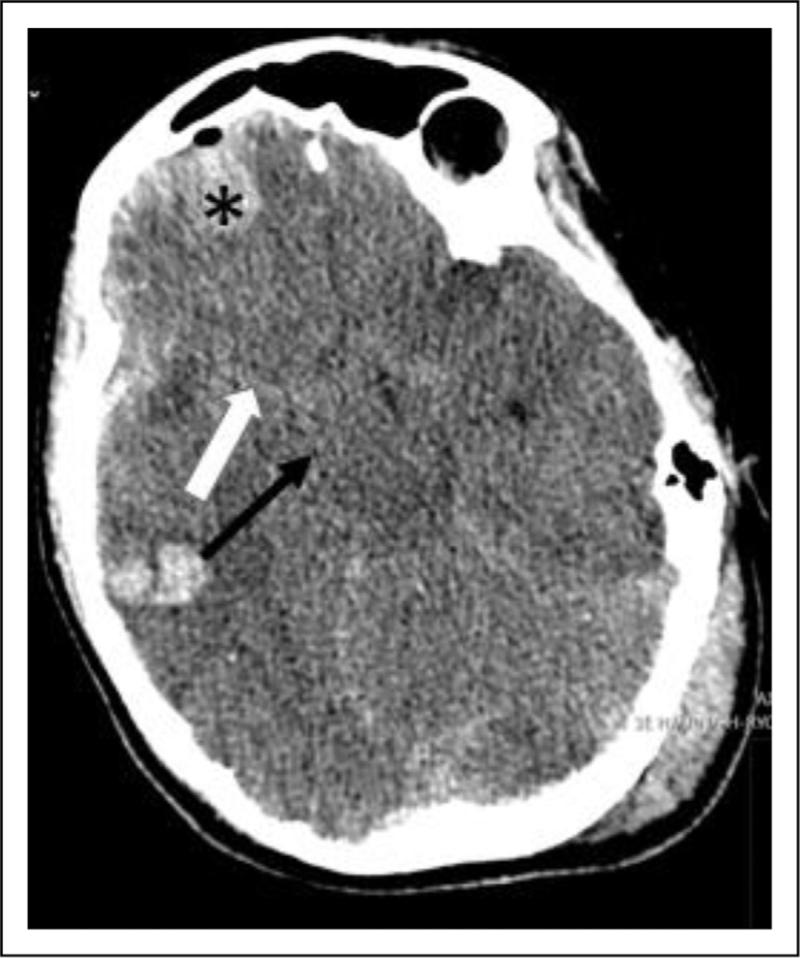

Prehospital management of sTBI should adhere to Advanced Trauma Life Support (ATLS) principles. Maintaining oxygen saturation and blood pressure within target ranges on-scene by anesthetist, emergency physician or trained paramedics has resulted in improved outcomes. Emergency department (ED) management prioritizes airway control, stable blood pressure, spinal immobilization, and correction of impaired coagulation. Noninvasive techniques such as optic nerve sheath diameter measurement, pupillometry, and transcranial Doppler may aid in detecting intracranial hypertension. Osmotherapy and hyperventilation are effective as temporary measures to reduce intracranial pressure (ICP). Emergent computed tomography (CT) findings guide surgical interventions such as decompressive craniectomy, or evacuation of mass lesions. There are no neuroprotective drugs with proven clinical benefit, and steroids and hypothermia cannot be recommended due to adverse effects in randomized controlled trials.

Advancement of the prehospital and ED care that include stabilization of physiological parameters, rapid correction of impaired coagulation, noninvasive techniques to identify raised ICP, emergent surgical evacuation of mass lesions and/or decompressive craniectomy, and temporary measures to counteract increased ICP play pivotal roles in the initial management of sTBI. Individualized approaches considering the underlying pathology are crucial for accurate outcome prediction.